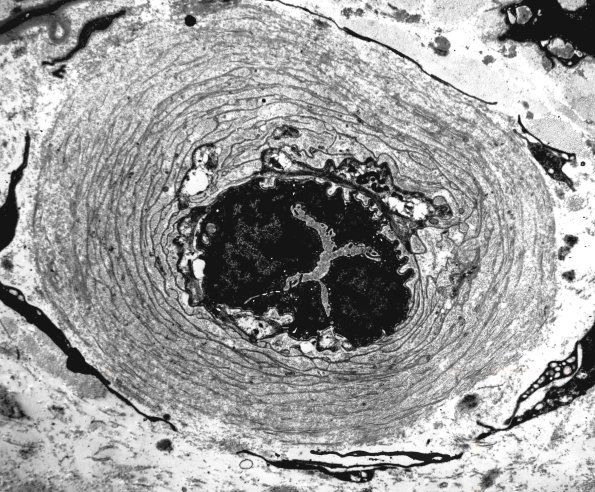

0A1 This is a typical classic diabetic type of endoneurial vascular thickening seen in diabetic neuropathy and consists of multiple concentric basal laminae largely devoid of cytoplasm. (electron micrograph)